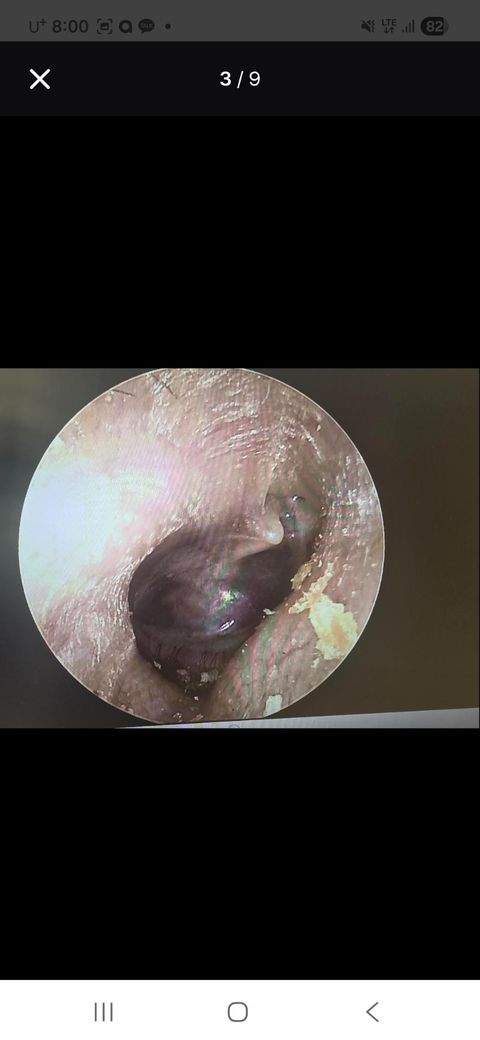

고막상태: 삼출물은 없으나 retraction 심하며 이랑 Adhesion 이 있음

고막 사진 및 발사바 했을때 사진 및 검사한 사진 첨부하였습니다.

• 3번 째 사진

우선 검사 소견을 정리하면, 고막은 삼출물 없이 뚜렷한 함몰(retraction)과 유착(adhesion)이 관찰되며, 순음청력검사에서는 양측 모두 20 dB 내외로 경도의 청력 저하가 있습니다. 임피던스 검사에서는 오른쪽 귀의 고막 컴플라이언스가 3.06 ml로 매우 높고 압력 정점이 확인되지 않는 반면, 왼쪽은 -296 daPa의 음압과 0.84 ml로 감소된 컴플라이언스를 보입니다. TTAG 및 소노튜보메트리 결과에서는 양측 이관 기능이 모두 비정상적 패턴을 나타내고 있습니다.